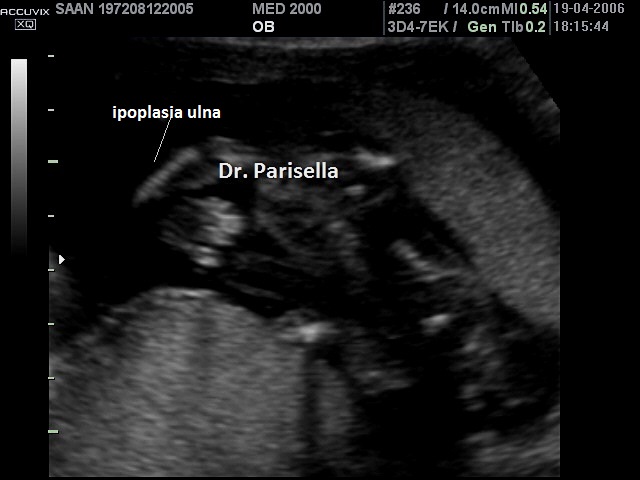

Sindrome di Langer o Nanismo Mesomelico di Langer    OMIM 249700

Segni principali:

mesomelia

ipoplasia ulna

ipoplasia fibula

ipoplasia radio

ipoplasia tibia

tibia ricurva

radio ricurvo

incurvamento della mano in senso ulnare